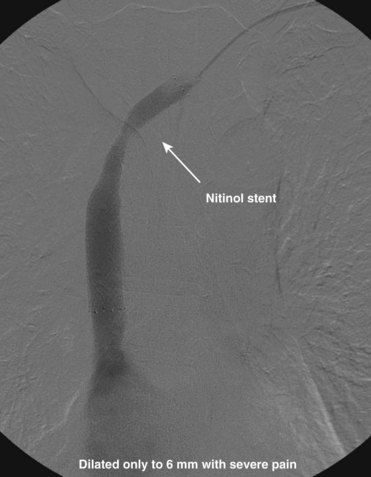

After overnight catheter-directed thrombolysis, a venogram is performed to assess the patency of the axillosubclavian vein (Fig. 18-7). Usually, overnight thrombolysis is sufficient to clear the associated thrombus, but in certain patients a second day of thrombolysis may be necessary. As with any thrombolysis procedure, the patient is informed of the potential risk of bleeding and monitored carefully as well as with fibrinogen levels. A venogram is then performed in a provocative position to assess the amount of compression and secure the diagnosis. We usually abduct and externally rotate the arm over the patient’s head. The area of compression on the vein is usually still present after thrombolysis (Figs. 18-8 and 18-9). Angioplasty can then be performed if there is a persistent high-grade stenosis (Fig. 18-10). A low-pressure balloon is used not solely to treat the venous obstruction but also to assess the amount of fibrosis and neointimal damage because a severely damaged vein may require a venous patch at the time of surgical decompression. The surgical decompression may be performed from a transaxillary or supraclavicular approach. A portion of the first rib along with the tendinous attachment of the transected anterior scalene muscle is usually removed (Fig. 18-11).

The central venous stenosis not only can be symptomatic with severe arm swelling but also may limit the function of a hemodialysis access. The treatment of central vein stenosis associated with hemodialysis is traditionally angioplasty. Unfortunately, the 1-year patency of these treatments has been reported to be between 10% and 30%, and the use of multiple additional procedures to maintain secondary patency is the rule. The initial use of stents to treat central venous stenosis has been discouraged because of a similar patency rate to that of angioplasty and the possibility of stent compression in the thoracic outlet. In addition, there are no U.S. Food and Drug Administration (FDA)–approved uncovered stents for the venous system. Even though the results from angioplasty are limited, endovascular dilatation of these stenoses is preferred over surgical options because of its availability, noninvasiveness, low risk of morbidity, and ability to repeat as needed. DOQI guidelines recommend stent placement for central lesions that recur within 3 months after angioplasty and demonstrate immediate vessel recoil greater than 50% after angioplasty and vessel perforation. The patency of a stent in central venous stenosis is similar to that of angioplasty, but the ability of retreatment becomes limited (Figs. 18-12 and 18-13). The use of covered self-expandable stents has shown promise, particularly in the setting of peripheral dialysis graft anastomotic stenoses. Their use will likely increase in the central veins; however, the operator needs to be careful in not excluding other draining veins with a central covered stent.